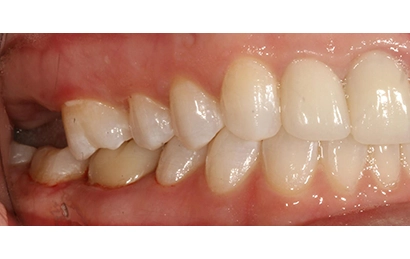

Chief Complaint: The patient presented with an upper right lateral incisor exhibiting mobility. Further examination revealed a history of endodontic treatment combined with root fracture.

Intraoral Assessment: Porcelain crowns were present on the upper right lateral and central incisors. The upper right central incisor displayed a root canal treatment, a periapical lesion, and a root fracture accompanied by discolored and inflamed gingiva. The lateral incisor had a periapical lesion deemed untreatable by the endodontist. The gingival papilla was receding between these teeth, manifesting as a visible black triangle.

Intraoral pictures of the initial condition